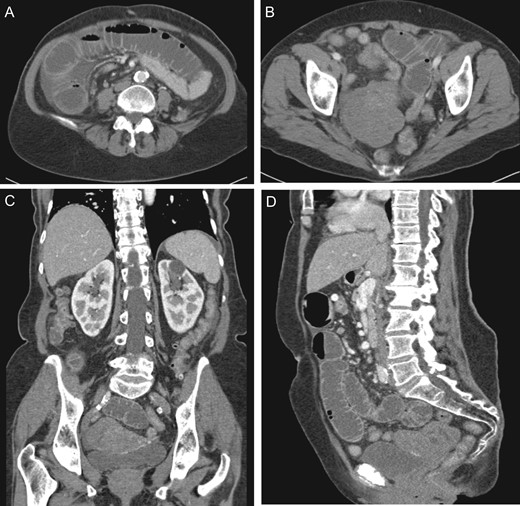

While awaiting evaluation by gynecologic oncology, she presented acutely with nausea, vomiting and abdominal pain. At that time, she was found to have a small bowel obstruction (SBO) on CT imaging with concern for a transition point near her previously visualized pelvic mass (Fig. 2). She was given a trial of non-operative management, including nothing by mouth and nasogastric decompression; however, given her persistent abdominal pain and high nasogastric tube (NGT) output, it was thought best to proceed with operative intervention.

(A) Dilated small intestine with small amount of ascites. (B) Large heterogeneous pelvic mass. (C) Coronal view pelvic mass (arrow) with compression of bladder (arrow head). (D) Sagittal view pelvic mass.